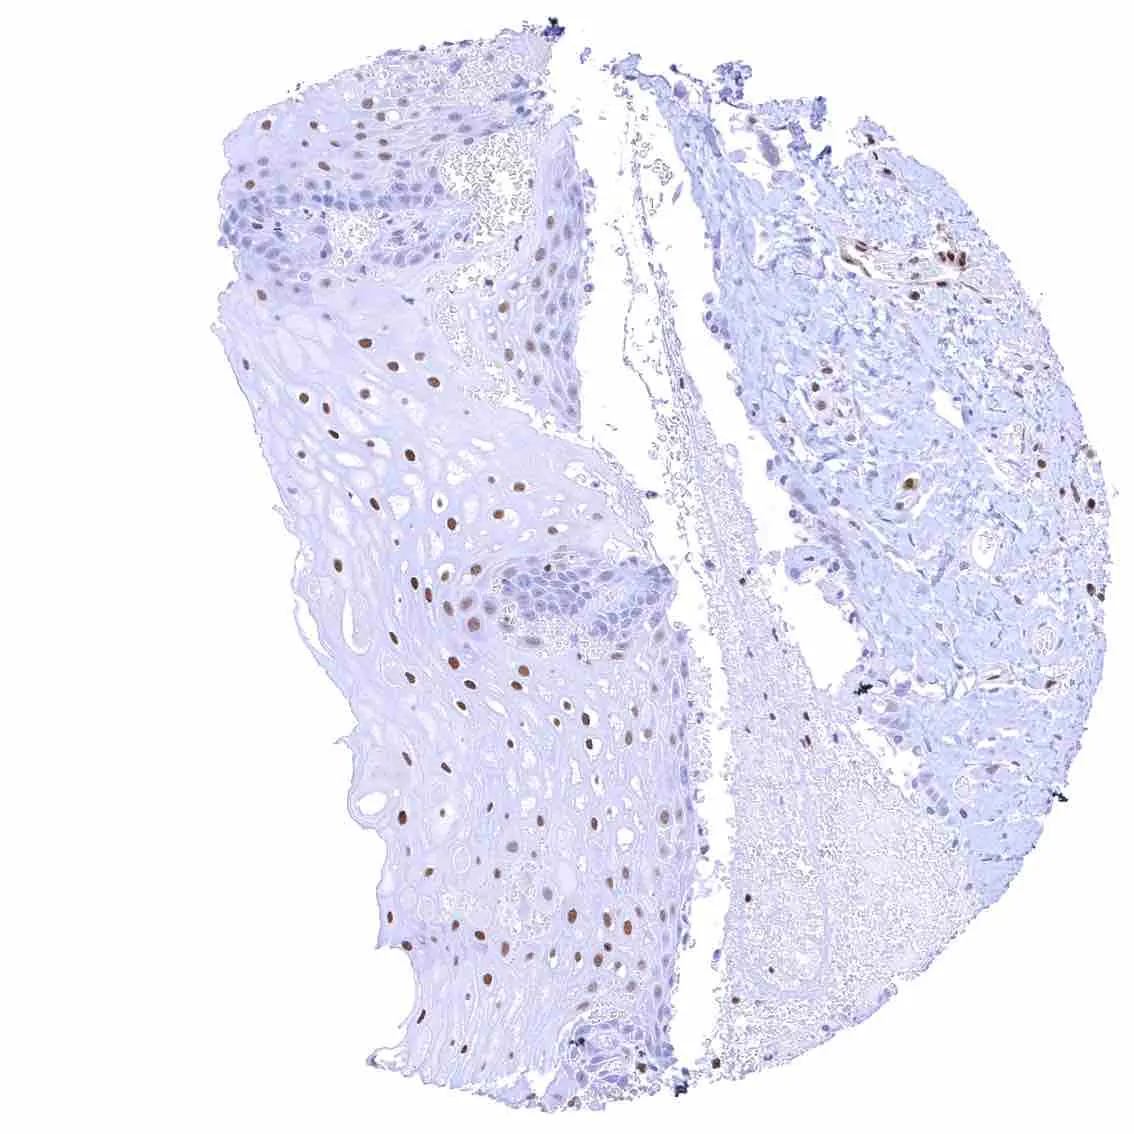

Esophagus, squamous epithelium – Nuclear staining of squamous epithelial cells predominates in the more mature cell layers (top 50_ of the epidermis).